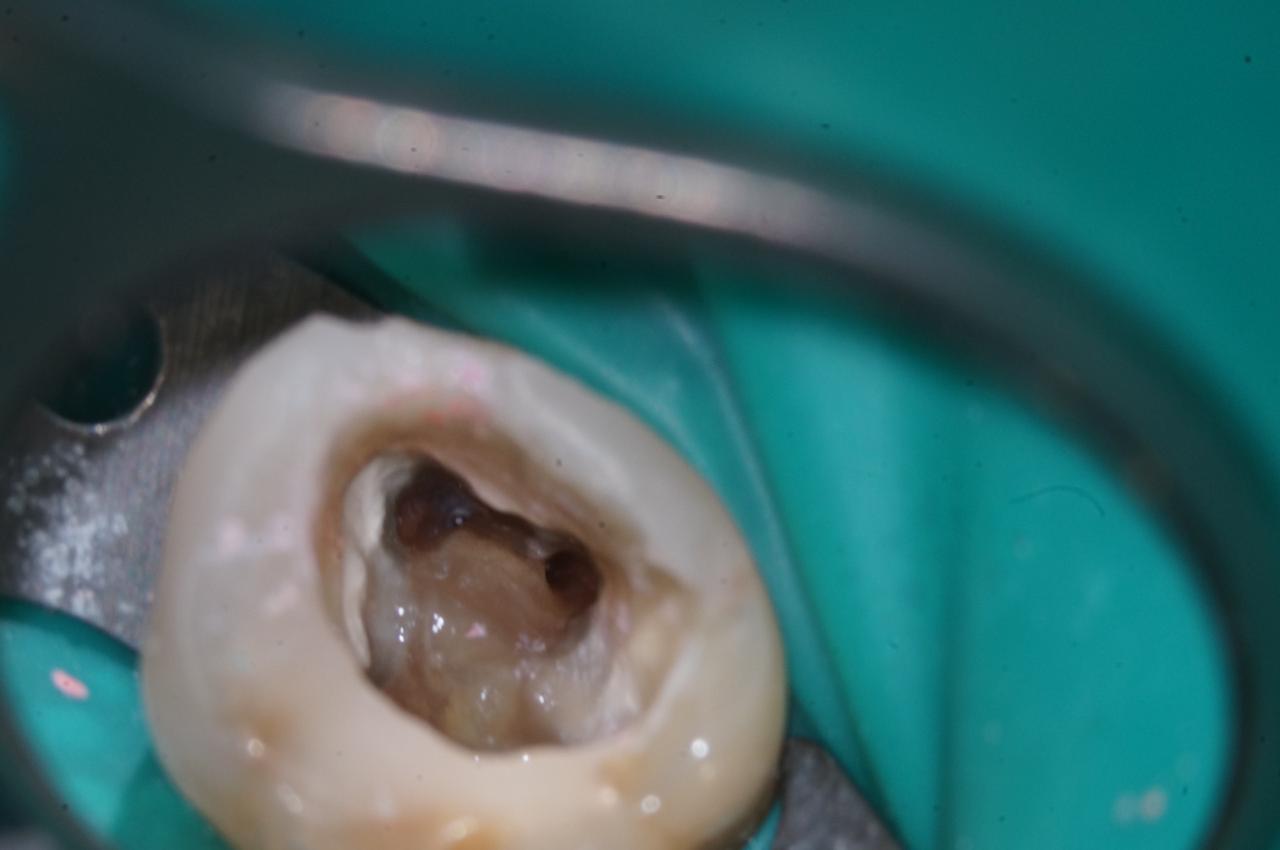

• Сразу видно куда больше, чем просто глазом. Когда я первый раз взглянул для контроля вмешательства, то мне сразу же захотелось переделать всё. Дело не в глазах, дело в мозге. Картинка в мозгу была в 15 раз больше. Суть успешного лечения тех же корневых каналов в том, чтобы их правильно расширить, вымыть оттуда всю грязь, высушить и потом запломбировать. Протокол не менялся десятилетиями, менялись инструменты и химия. Глазами вы просто видите, что отмыли канал хлоркой (гипохлоритом натрия) и пломбируете. А микроскоп показывает, что там ещё лежит всякий мусор: пломбировочный материал другого доктора, пульпа, ворс от бумажных штифтов (которыми канал сушится). Скажу честно: это не моя идея привезти микроскоп, это один из врачей сам попросил для каналов. Но после этого показал всем, и мы пересели за них. При таком увеличении можно использовать сам бур как линейку. Вот для виниров мы хотим оставаться в пределах эмали, защищающей дентин. Если надо убрать 0,2 миллиметра, то это пятая часть бура толщиной 1 миллиметр. Попробуйте так без микроскопа.

Для обывателя всё это не очень важно. Важно то, что мы умеем спасти почти любое воспаление. Процент успешных случаев вырос до 90 % по сравнению с 60–70 % обычной статистики перелечивания корневых каналов. Появляется такая суперважная вещь: если зуб продолжает болеть после вмешательства в канал, то вы точно знаете, что дело не в канале. Это критически важно для того, чтобы не открывать его второй раз. Потому что есть уверенность, что чистка была качественная.

Смотрите, вот зуб на платке, изолирующем его от слюны (к другой стороне зуба всё ещё прикреплён пациент):

image

А вот так его видно в микроскоп:

Видите? Канал чистый.